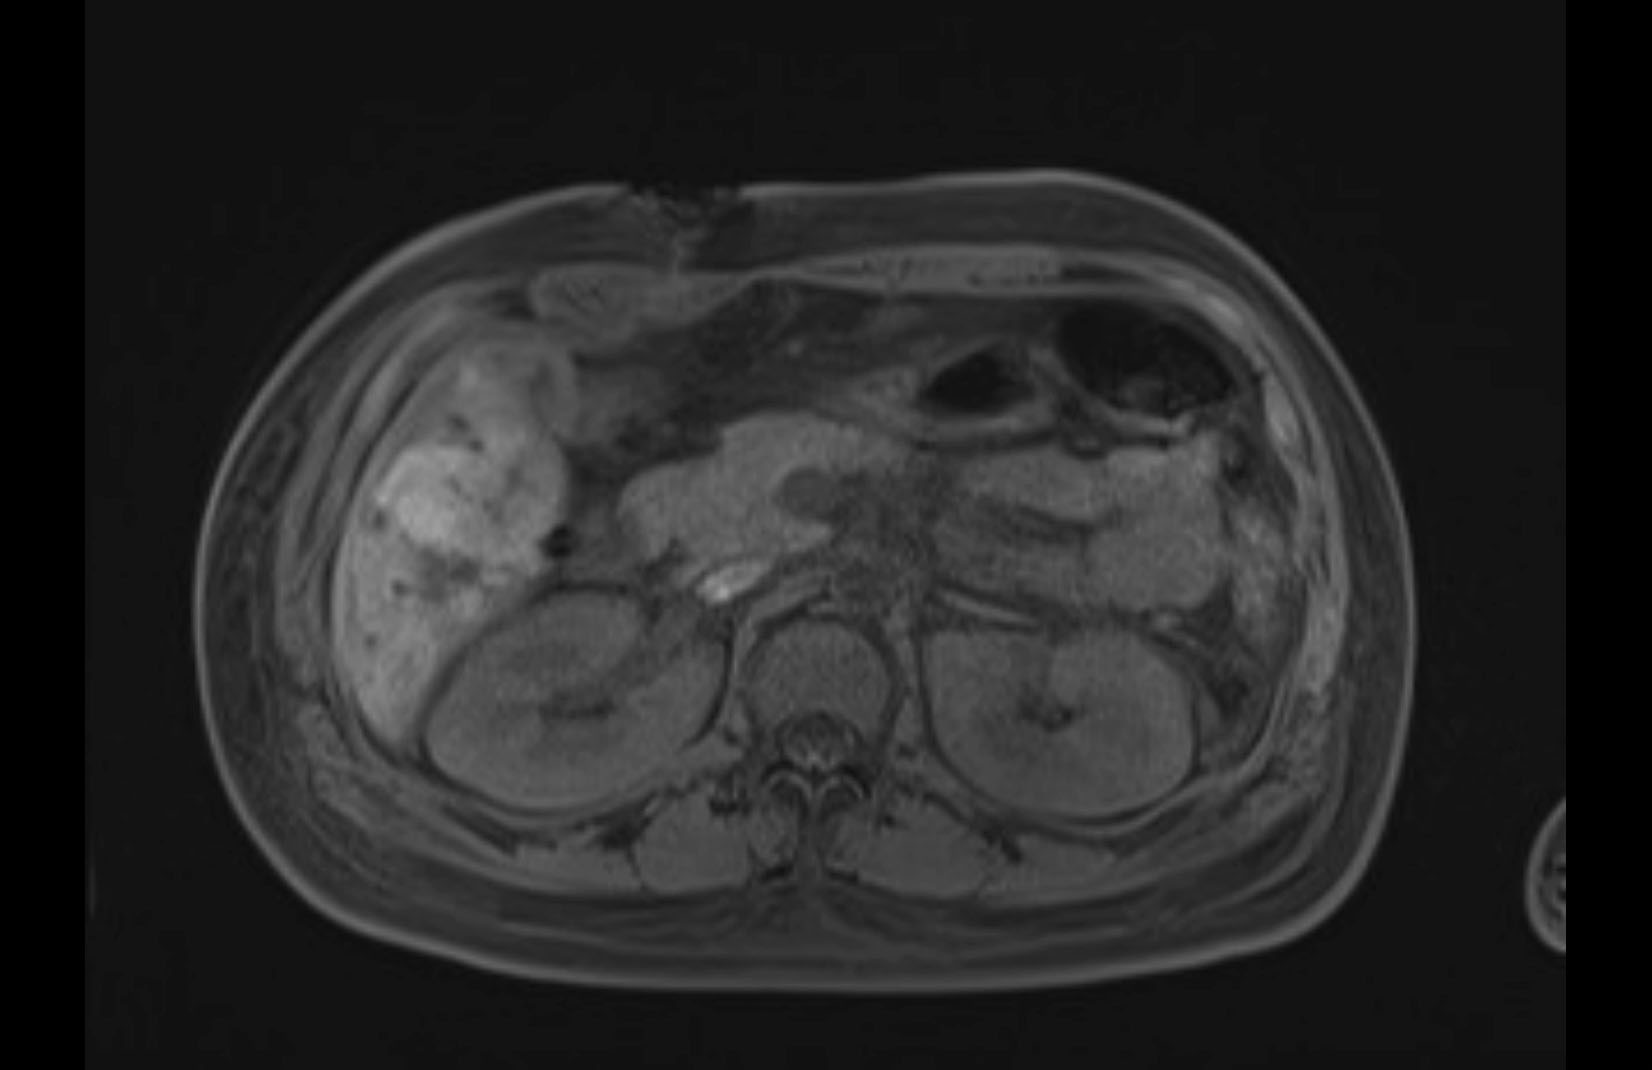

Imaging Analysis

Look through the patient's CT scan to identify any areas of concern for the necessary procedure.

MRI T2

Based on initial findings, which issue(s) would you be most concerned about?